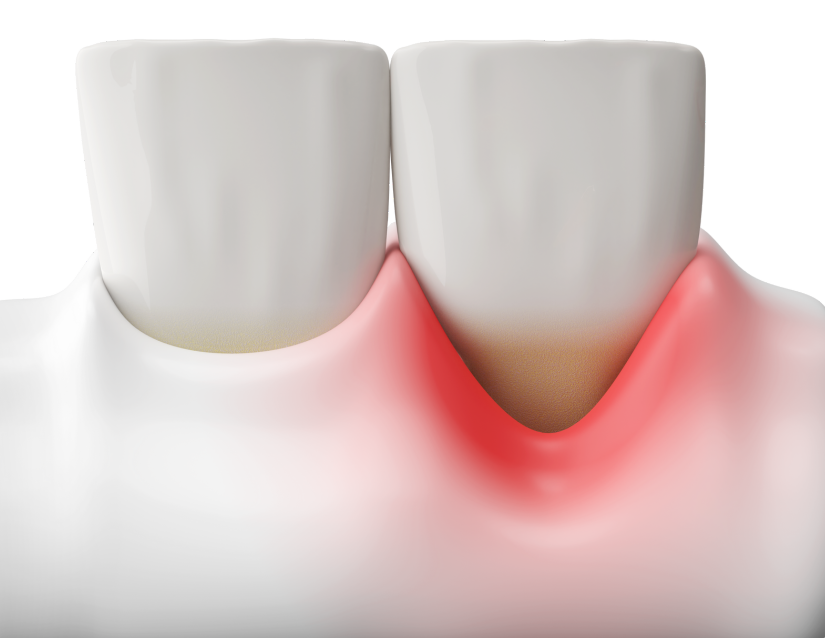

Gingivitis

La gingivitis se caracteriza por la inflamación y el enrojecimiento de las encías, causados por la acumulación de placa bacteriana.

• Enrojecimiento y sangrado, especialmente al cepillarte los dientes

• Inflamación de las encías (principalmente por  acumulación de placa bacteriana).